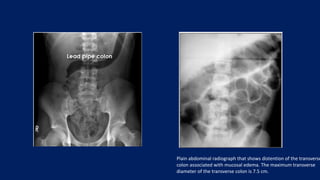

Plain abdominal radiograph that shows distention of the transverse

colon associated with mucosal edema. The maximum transverse

diameter of the transverse colon is 7.5 cm.